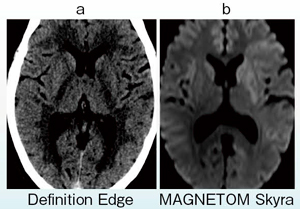

図6 SAFIREを用いた陳旧性視床梗塞の描出

a:64列MDCT with SAFIRE

b:他社製16列MDCT

頭部の検査において,頭部単純CTはきわめて重要である。最初に頭部CTにSAFIREを適用した時には,ノイズが軽減し,非常にきれいな画像が得られると感じた。スパイラルで再構成するよりシーケンシャルで撮影する方が画質が向上するため,頭部CTではチルト機構が必要と考える。SAFIREのstrengthは1〜5までのレベルがあり,強くするほど高いノイズ低減効果が得られるが,当院ではstrength 2までとしている。その場合,管電圧120kV,435mAsの撮影条件でCTDIvol 69.58mGyとなり,被ばくは従来通りとしたままで画質を向上させることができる。SAFIREを用いた画像の視認性は高く,陳旧性の脳梗塞も明瞭に見えるようになった(図6)。今後,さらに撮影条件の最適化を図る予定である。